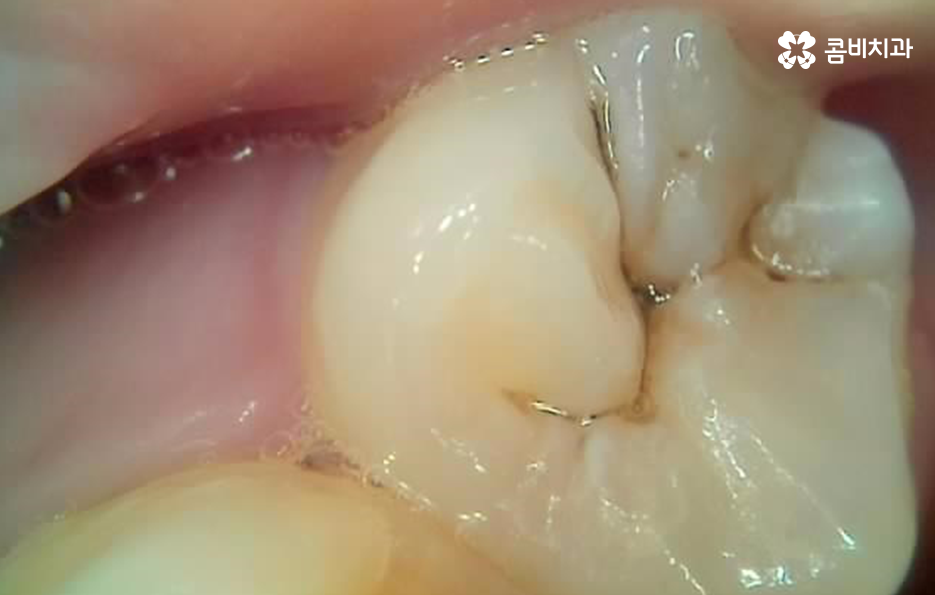

자연치아의 수명을 보존하는데 있어서 치과 보철 치료에 대해 잘 이해하는 것은 무척이나 중요할 수 있는데요. 많은 분들이 초기에는 간단하게 레진 치료를 할 수 있겠지만 보철물의 관리가 잘 안되어 재치료를 거듭할수록 자연치아의 손상이 크고 작게 발생할 수 밖에 없고 점점 더 큰 치료로 이어지면서 자연치아의 수명도 저하되는 경우가 많이 있어요

특히 치아 신경치료로 이어지거나 치아 뿌리 쪽에 충치가 깊어지면 치아 수명이 급격히 저하되고 발치로도 이어질 수 있다는 점에서 현재 어금니 레진 교체에 대한 고민을 한다면 현재 치아 상태에 적합한 치료도 제때 잘 받아주시길 바라며 무엇보다 보철물 관리에도 힘써서 비슷한 문제가 재발하지 않도록 주의하시길 바라고 있어요